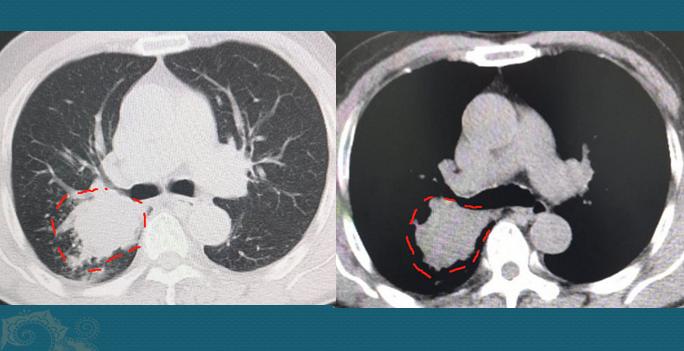

我们先不争论这些,看看这个病人的CT片:

右侧肺门区一个不规则肿块,最大径线4.6cm,远侧肺组织里有一些小点片状炎症,这是由于肿瘤堵塞气道,引起的阻塞性肺炎。

这个肿瘤经胸外科主任会诊,已经失去手术机会。经支气管镜病理确诊为非角化型肺鳞癌。